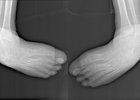

Рентген мальчика с деформацией стоп. Фото пресс-службы Ивано-Матренинской детской клинической больницы

Врачи-травматологи Ивано-Матренинской больницы провели операцию ребенку с деформацией стоп, которая не позволяла даже надеть обувь. Вмешательство прошло в два этапа, сообщает пресс-служба учреждения.

19 сентября 2025 года ребенку провели первую операцию на правой стопе. После этого мальчика отправили домой для восстановления и подготовки ко второму этапу. Спустя два месяца провели второе вмешательство. Обе стадии работы представляли собой реконструкцию костей стоп и длились около часа.

Глеб Большаков, заведующий отделением травматологии и ортопедии: — Сложность операции была в том, что мы поздно «нашли» этого пациента, то есть до 11-летнего возраста он нигде не лечился, поэтому деформация была уже тяжелой степени. Обычно это исправляется с 5-летнего возраста.